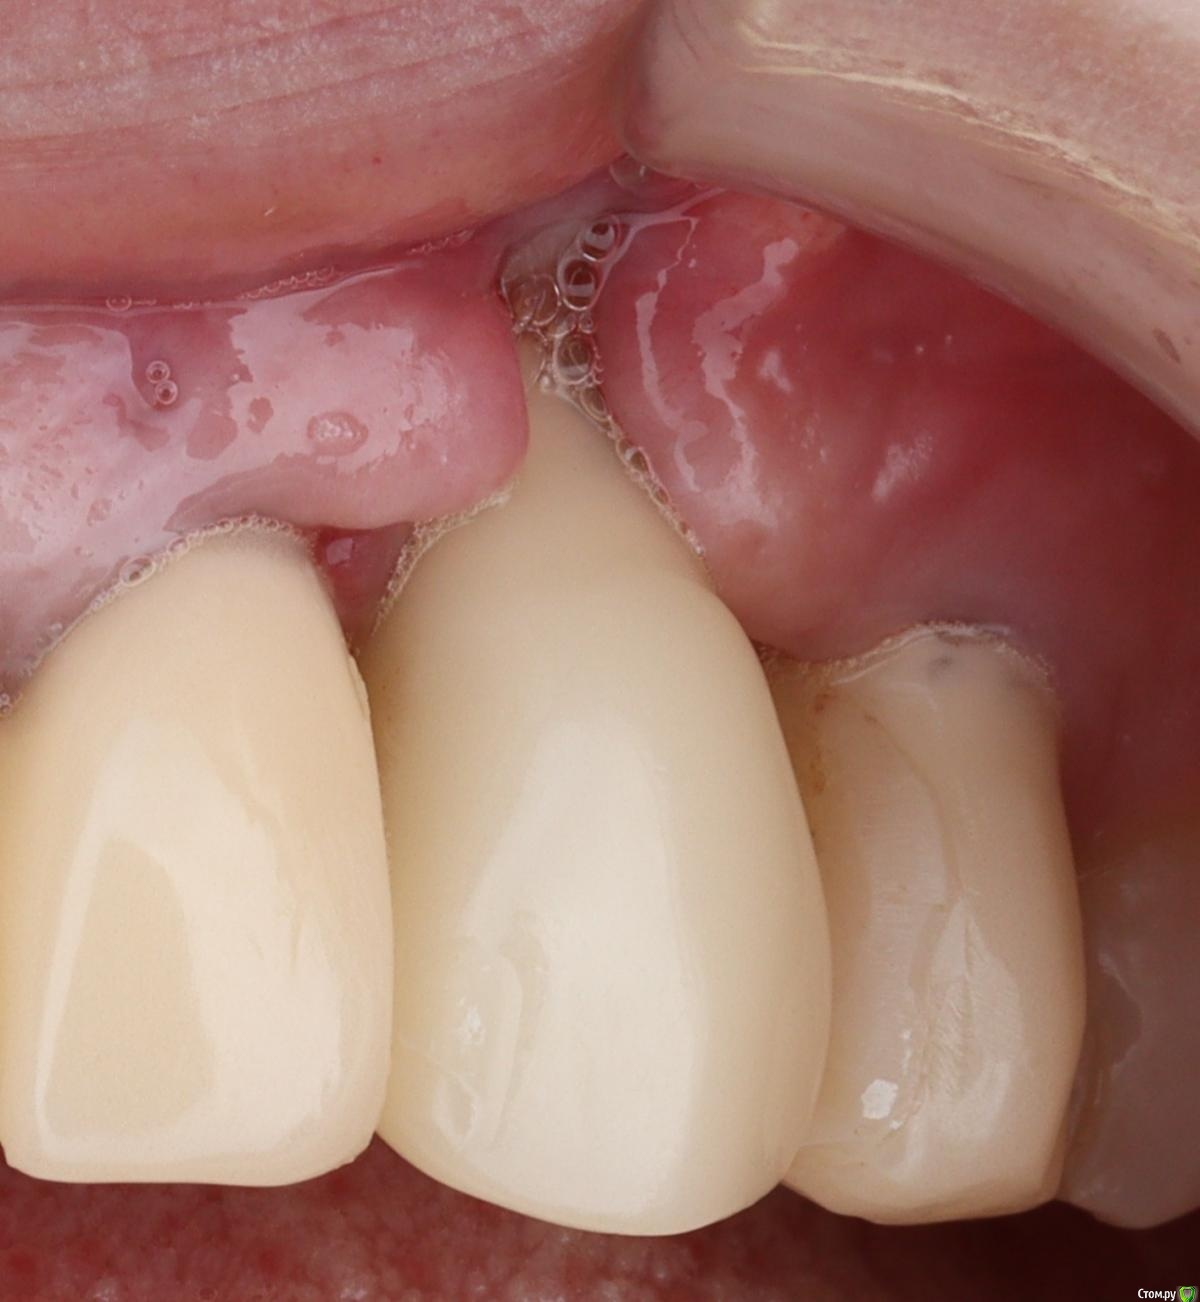

Irouil Опубликовано 4 февраля, 2021 Поделиться Опубликовано 4 февраля, 2021 (изменено) я так понимаю на первой фотке проблема была в толстой поддесневой части. жаль промежуточных этапов не скинули.Фотки тут для примера результата через неделю после использования описанного метода, никаких особо этапов - во время самой хирургии я не фотографирую, к сожалению. Истончать тут для того, чтобы хватило места для питающей ножки - если коронка будет слишком толстая у основания, то она передавит лоскут крестально, ведь в лоскуте посередине перфорация через которую коронка фиксируется к импланту по типу "шашлыка"-пончо. А если интересна проблема, то она в расстоянии от платформы до зенита (на втором фото) порядка 7 мм. И тут уже была неудачная попытка что-то сделать, судя по всему - как раз натянуть коронарный лоскут.странно что никто коронально смещенный не поддержал. разные варианты предложилиА в чем преимущества, на Ваш взгляд? Как мне кажется, в Вашем кейсе с апикального направления тянуть далеко, прикрепленки не безгранично, риски потерять то, что есть - высокие. А сосочки совсем рядом, причем отличные по всем параметрам. Изменено 4 февраля, 2021 пользователем Irouil Ссылка на комментарий